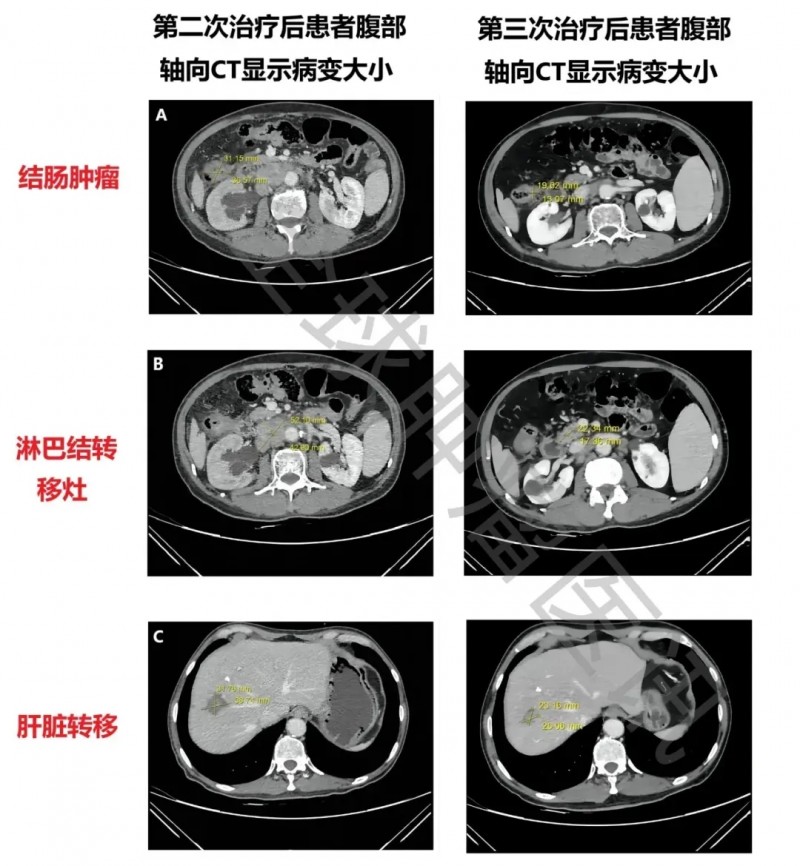

此次联合治疗效果显著:一是所有病灶均明显缩小,结肠肿瘤从3.7cm×3.1cm缩至2.1cm×1.7cm,腹膜后淋巴结转移灶从5.2cm×4.3cm缩至2.3cm×1.4cm,肝脏肿瘤从3.9cm×3.2cm缩至2.9cm×2.3cm(详见下图),最终达部分缓解(PR)(对比第二次治疗,此次肝脏转移灶首次缩小);二是肿瘤标志物显著下降,癌胚抗原(CEA)从30.1μg/L降至4.3μg/L,CA19-9从62.64kU/L降至23.97kU/L。

▲图源“Cureus”,版权归原作者所有,如无意中侵犯了知识产权,请联系我们删除